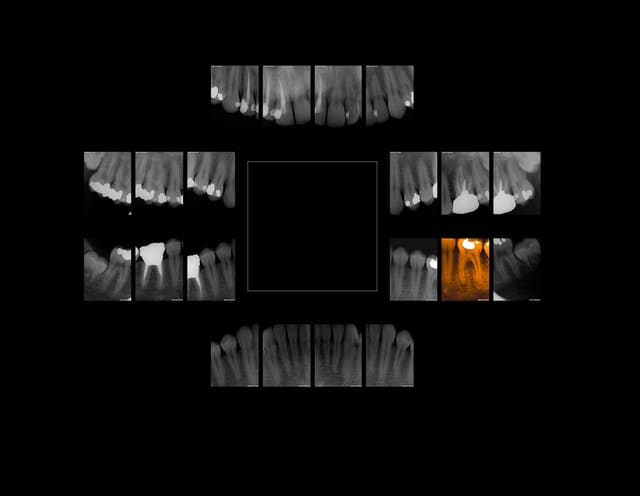

9h 45. Xavier 16 ans Nouveau patient. Urgence douleurs région 3 molaire. Reprise carie sous amg. C'est pas moi qui ai fait les pulpecs hein (qui sont correctes ma fois)! Re z56 !))))))

On est saisi par le succès des bbd à 25 euros.)))))

Xavier 16 ans ttbiqk - Eugenol